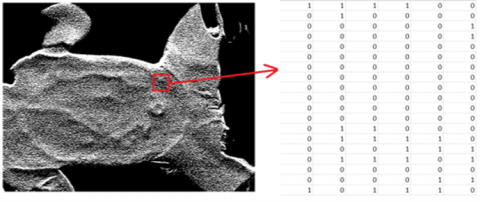

Consequently, a matrix that contains the temperature changes was obtained. The matrix has negative and positive values, as shown in Figure 7 and values that are greater than zero are equal to 1, equal or smaller than zero are equal to 0 (Eq. (2)).

$\left\{\begin{array}{l}1, \frac{d f}{d x}>0 \\ 0, \text { others } \end{array}\right.$           (2)

Figure 7. Matrix of temperature changes

where, g(x) is the binary matrix obtained from the thermal map as shown in Figure 8.

Figure 8. Binarized thermal map visualization and related matrix